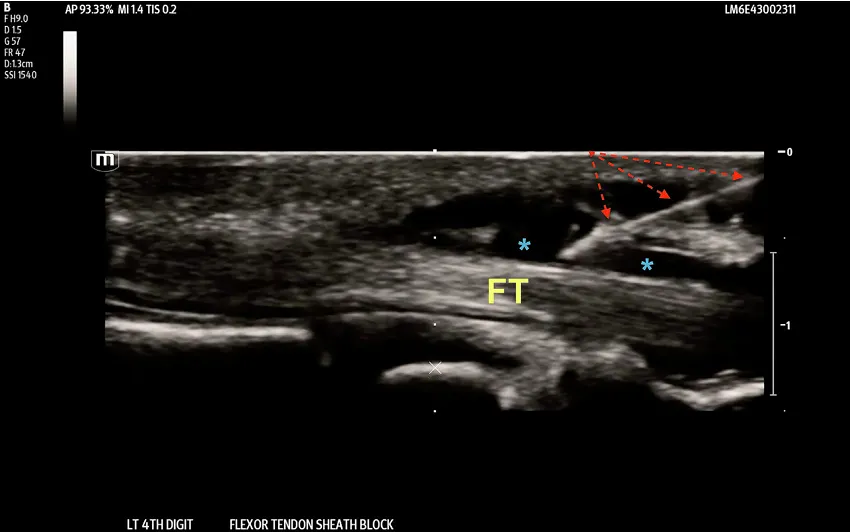

Fig. 3. In-plane needle technique showing 27-gauge needle (dashed red arrows) in the flexor tendon sheath space (blue asterisks). FT- Flexor Tendon (yellow). (For interpretation of the references to colour in this figure legend, the reader is referred to the web version of this article.)